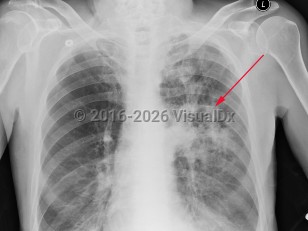

Chest pain, Pleural effusion, 50-59 year old Female

Pleural effusionPleural effusion

Lung cancerLung cancer

TuberculosisTuberculosis